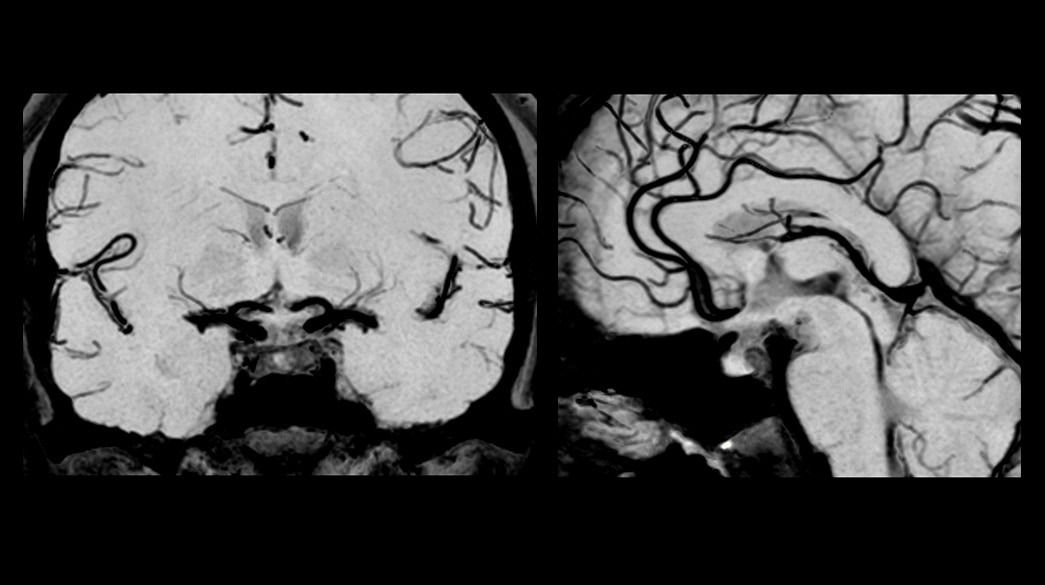

Neurological MR imaging applications

Diagnostic confidence and consistency